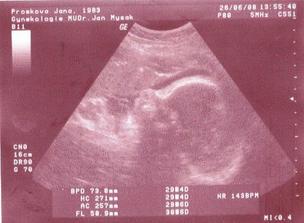

26.6. další velký UTZ, vše je OK, jenom jsme opravdu malincí...o tři dýny menší než bychom měli být...tak snad to ještě dorosteme, jinak je vše v pořádku :o)